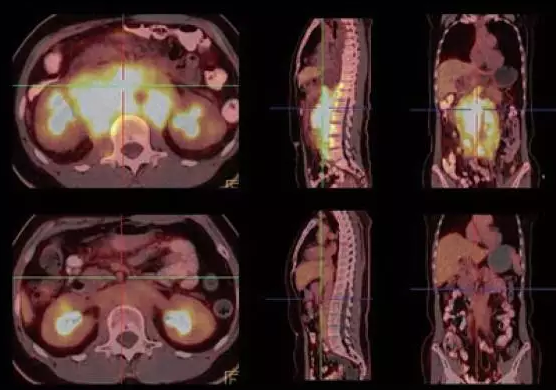

患者,女性,52 岁,体重67Kg,身高164cm。因发热就诊,影像检查发现淋巴瘤,化疗前行PET\CT 显像进行诊断与分期,化疗4 疗程后再次进行PET\CT 显像观察疗效。超高清PET\CT 影像,化疗前后变化清晰显示。

图1:十字光标:腹腔淋巴瘤化疗前FDG摄取显著增高,淋巴结融合,体积较大,化疗后基本正常,未见明显异常FDG摄取增高灶。(上排为化疗前,下排为化疗后图像。)